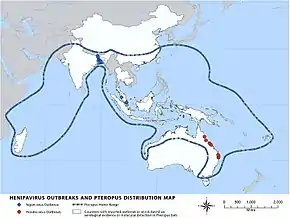

Outbreaks

Nipah virus outbreaks have been reported in Malaysia, Singapore, Bangladesh and India. The area is known as the Nipah Belt. The highest mortality due to Nipah virus infection was found in Bangladesh, where outbreaks are typically seen in winter.[23] Nipah virus was first seen in 1998 in peninsular Malaysia in pigs and pig farmers. By mid-1999, more than 265 human cases of encephalitis, including 105 deaths, had been reported in Malaysia, and 11 cases of either encephalitis or respiratory illness with one fatality were reported in Singapore.[24] In 2001, Nipah virus was reported from Meherpur District, Bangladesh[25][26] and Siliguri, India.[25] The outbreak again appeared in 2003, 2004 and 2005 in Naogaon District, Manikganj District, Rajbari District, Faridpur District and Tangail District.[26] In Bangladesh there were further outbreaks in subsequent years.[27][6]

- September 1998 – May 1999: in the states of Perak, Negeri Sembilan and Selangor in Malaysia. A total of 265 cases of acute encephalitis with 105 deaths caused by the virus were reported in the three states throughout the outbreak.[28] The Malaysian health authorities at first thought Japanese encephalitis (JE) was the cause of infection which hampered the deployment of effective measures to prevent the spread of Nipah virus.[28]